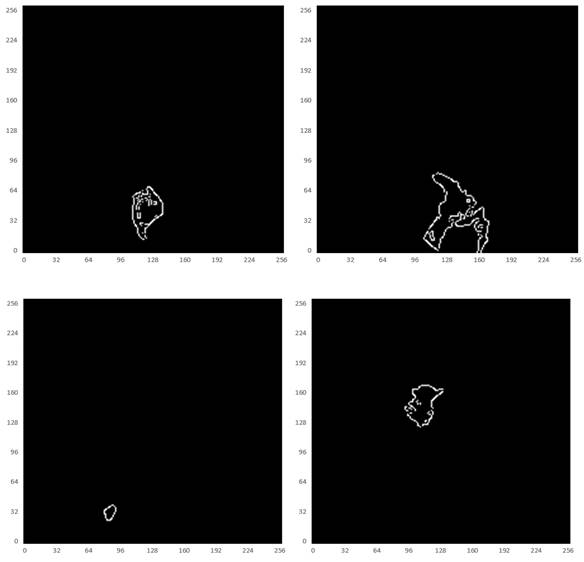

Fig 7

Illustration of the boundary ground truth of MRI scans from four different patients that were manually annotated by clinic experts.

J Cancer Image

Referring to Fig. 2, the second convolutional layer was processed to map the edge information to necessary output categories. Considering that the tumor is immersed in the glands of breast tissues, the boundary information cannot be easily detected. However, the smoothness of the boundary features is one of the key factors to identify tumors. Therefore, the boundary attention module and the edge loss function were hereby designed to achieve accurate extraction of boundary features to improve the performance of tumor segmentation. The output of extracted boundary information was compared with the boundary ground truth, as shown in Fig. 8. The output of the tumor edges was visually matched with boundary ground truth.